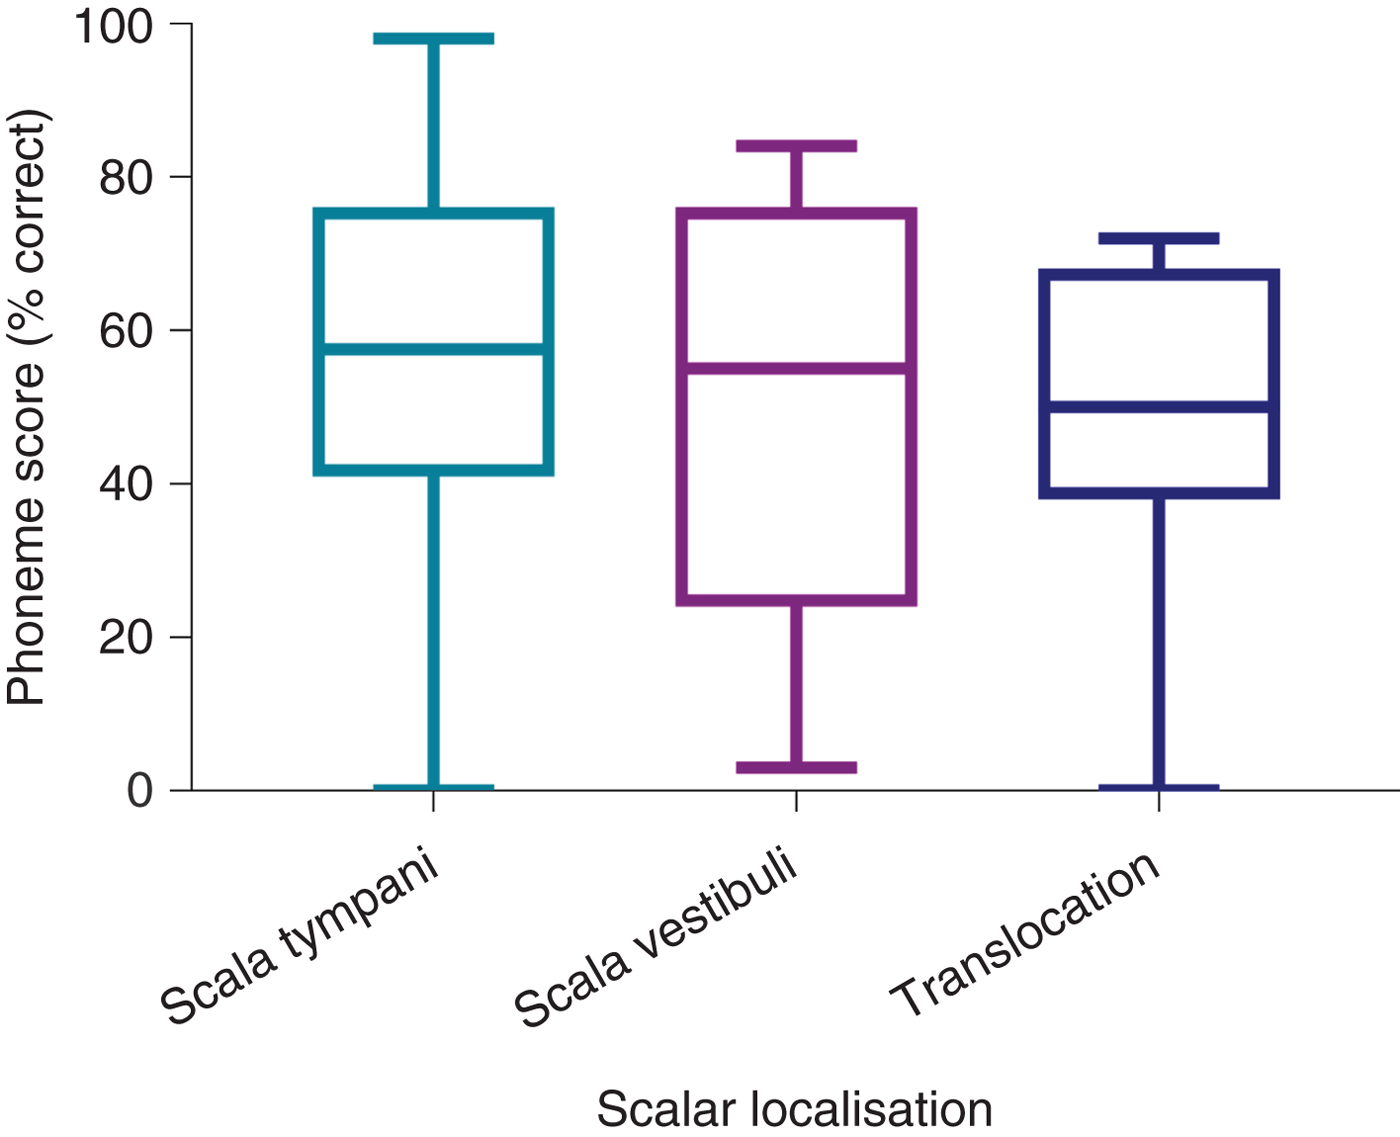

Comparison of post-operative phonemes scores between the CI512 electrode localisation groups revealed better scores for scala tympani localisation, at 3 and 12 months post-implantation, but without statistical significance (Table 2 and Figure 5). When the pre-lingual patients were excluded and the post-lingual patients analysed, there were significant differences between the scala tympani group and the other two groups (scala vestibuli and translocation) (p = 0.013). These differences were significant at 12 months post-implantation. Post-hoc analysis demonstrated significant differences between scala tympani and scala vestibuli groups (69.1 per cent vs 54.2 per cent; p < 0.05) and between scala tympani and translocation groups (69.1 per cent vs 50 per cent; p < 0.005) at 12 months post-implantation, but without significant differences between scala vestibuli and translocation groups (Table 3 and Figure 6).

Fig. 5. Twelve-month post-implantation phonemes scores of all patients with CI512 electrodes according to scalar localisation.

Fig. 6. Twelve-month post-implantation phonemes scores of post-lingual patients with CI512 electrodes according to scalar localisation.

The degree to which scalar localisation contributes to the speech recognition outcome is the most relevant endpoint for clinicians. Our findings demonstrated that intracochlear electrode placement has a significant influence on the variability of post-implantation speech recognition results. There was a trend toward better consonant–vowel–consonant word scores for the complete scala tympani insertion group of combined pre- and post-lingual recipients, compared to the scala vestibuli and translocation groups, but this did not reach significance. Analysis of the scala tympani group revealed a much higher proportion of pre-lingual recipients, which may explain the poorer results for that group. Previous studies examining scalar localisation have reported outcomes for post-lingual recipients only.

Given that poorer outcomes are expected in recipients with a pre-lingual component to their hearing loss, a further analysis that included only post-lingual recipients was performed, in order to minimise the variables. This comparison demonstrated that the scala tympani group speech performance scores were higher by 15 per cent on average, compared to the scala vestibuli group. Moreover, according to the regression analysis model, electrodes located in scala vestibuli, or translocated from scala tympani to scala vestibuli, independently reduced the 12-month post-implantation phoneme scores by 10.5 per cent, while no significant difference was found between scala vestibuli and translocation localisation.